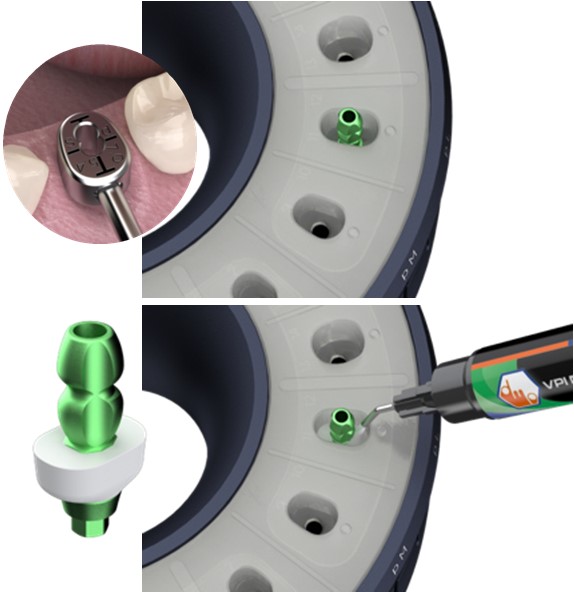

Pasul 5 – Procesul de duplicare a amprentei după fabricare

Asistentul instalează un stâlp de imprimare a stocului în același puț al matriței care a fost folosit pentru fabricarea bontului personalizat de vindecare (de exemplu, pS).

El / Ea introduce apoi materialul compozit adecvat în spațiul deschis și vindecă ușor cu unul sau mai multe trepte.

Apoi dezinstalează postul de imprimare duplicat creat și continuă cu lustruirea suprafeței compozite și dezinfectarea corespunzătoare.

Procesul de duplicare a amprentei după fabricare se poate face după programarea la consultație, sau la operație sau chiar înainte de etapa de amprentă, deoarece necesită doar aproximativ 4 minute pentru a fi finalizată.